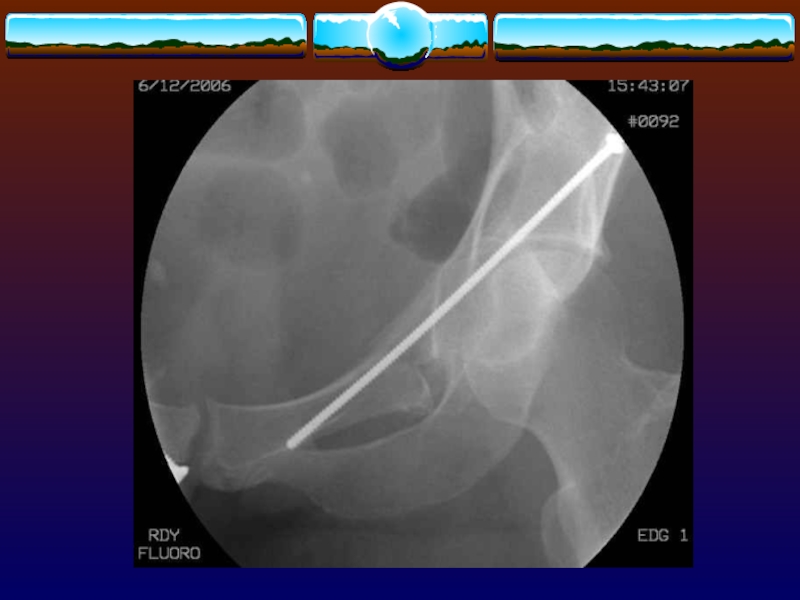

Слайд 103Восходящая уретрография

при выявлении признаков повреждения мочеиспускательного канала и переломах

с расхождением лобкового симфиза

Восходящая уретрография при выявлении признаков повреждения мочеиспускательного канала и переломах с расхождением лобкового симфиза